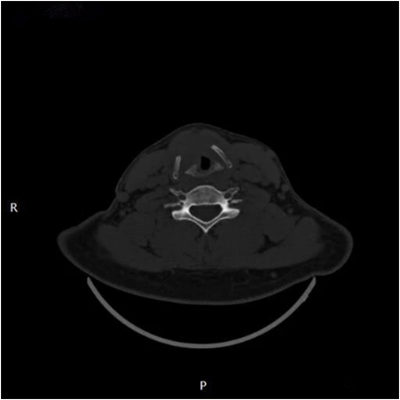

声门层面右侧声带增厚,呈结节状软组织密度影,边界尚可见,前联合及左侧声带前1/2受累,声门左偏,周围脂肪间隙小时,右侧甲状软骨骨质破坏。增强扫描呈轻度延迟强化。